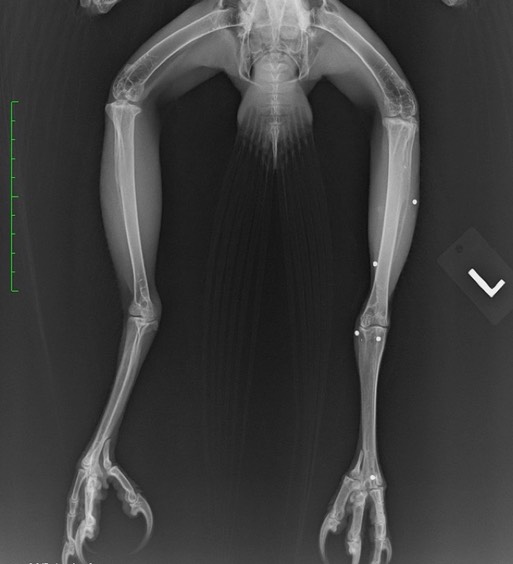

The third gunshot hawk was Red-tailed Hawk 20-565 from Eltopia, WA. There are 9 pellets or pellet fragments in the first x-ray (4 in the body, 1 in each wingtip, 1 in the neck and 2 in the head). The second x-ray shows 5 more pellets in the left leg and foot. There are multiple fractures in the major and minor metacarpals in the left wing. The wing has been splinted to immobilize the fractures. The hawk appears to be blind in his left eye. The hearing in the left ear may also be affected.

A further complication is a blood lead level of 24.3 micrograms/deciliter. That is subclinical lead poisoning and was caused by the hawk eating prey that had been shot with lead ammunition. We are chelating to remove the lead. There is reasonable hope that the metacarpals will heal and the wing will be fully functional. Assuming that is the case, the hawk will need further evaluation to see if he can catch wild game with his visual and possible hearing deficits. You can see why we are able to release so few gunshot birds.